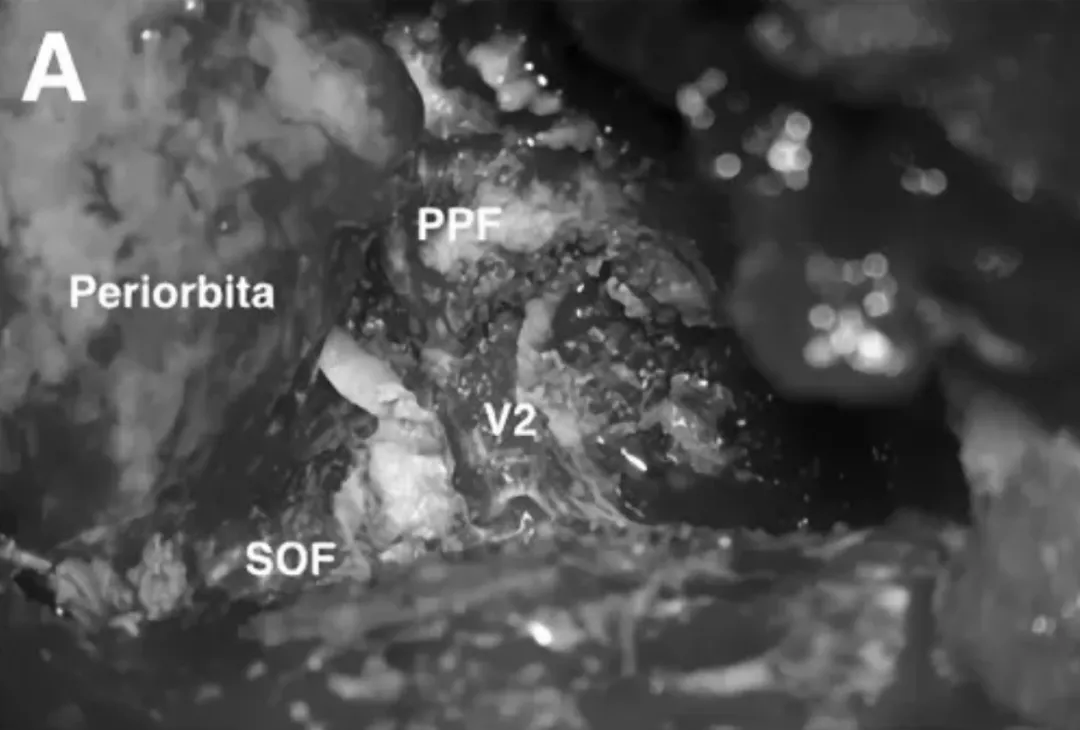

福教授经翼点入路开颅,剥离海绵窦侧壁后,行硬膜外前床突磨除术。切除硬膜内肿瘤、侵袭硬脑膜及眶周的肿瘤。使用脑膜补片对硬脑膜缺损进行水密封闭,然后暴露圆孔(FR)、翼腭窝(PPF),发现肿瘤沿V2神经鞘播散生长,磨除上颌窦(MaxS)部分壁后,打开蝶窦(SphS)。

SOF、PPF和V2暴露,注意保护神经血管,识别和定位肿瘤。

在V2和SOF之间可见上颌骨(MS),PPF移位。